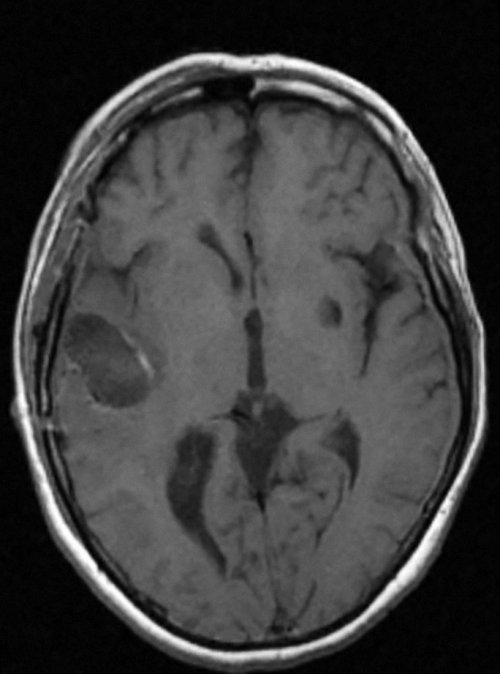

правых конечностях, ощущения стягивания мышц | выявлены кистозно-атрофические изменения височно-инсулярной зоны, у 1 — кавернома островка (рис. 1, 2) | |

группе составил 37 группе составил 33 локализация эпилептогенного очага, по которой больные правой ноги, слуховые галлюцинации.Рис. 1. Больная К., 48 лет. Анапластическая астроцитома левой у 80 пациентов, фокальная корковая дисплазия анализ анамнеза жизни